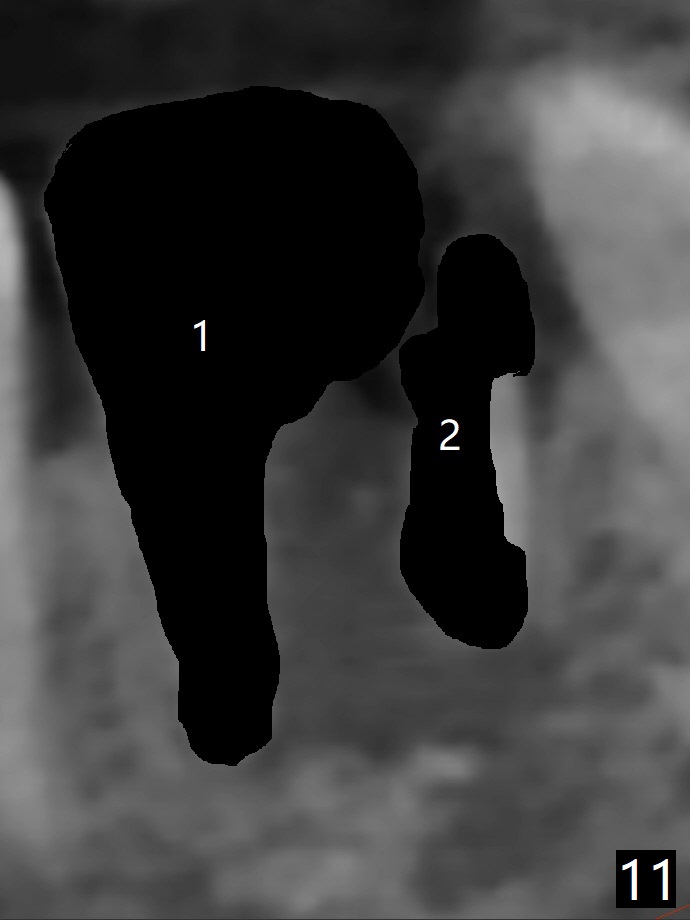

A 61-year-old woman with history of bruxism returns to clinic with chief complaint "I cannot chew bottom right. Top left has had pain and swelling before". Exam shows loose FPD at #31 (Fig.1) and necrosis of #14 (Fig.2). When the FPD is sectioned, the tooth #31 is found to have subgingival caries, filled with IRM (Fig.3). CT shows large PARL around MB and P roots of the tooth #14 (Fig.4), the fractured distal root of the tooth #19 with the low buccal plate (Fig.5) and a 5x10 mm implant being able to be placed at #30 (Fig.6). The crestal cortex (Fig.7 arrowheads) is thin in the edentulous area for several decades. The bone density is low (Fig.8, underprep). To place an implant over the pointed ridge, it should be trimmed prior to osteotomy (Fig.9). The bone loss associated with the fractured distal root is severe at #19 (Fig.10). After removal of the mesial root (Fig.11: 1), perform distal socket shield (2).